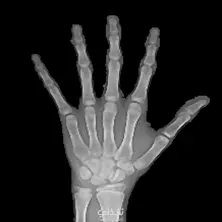

Bone age Assessment system

- طوّرتُ نظام تعلّم آلة للتنبؤ بالعمر العظمي - إخفاء الصور والكشف عن الكائنات - مطابقة القوالب - استخدمتُ Python وOpenCV - استخرجتُ الميزات ودرّبتُ النموذج - يُبرز خبرتي في مجال رؤية الحاسوب